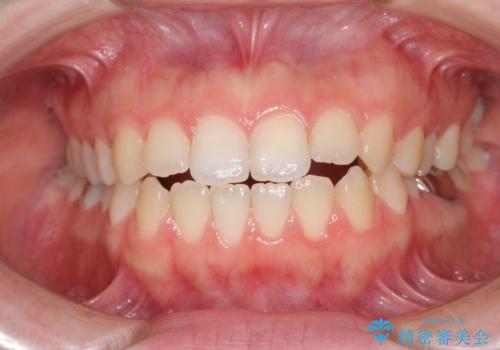

- 口元の膨らみが気になるとのことで来院された患者様です。

非抜歯で口元の突出感を少し改善させる治療も提案しましたが、最大限口元を引っ込めたいとのことでした。

上下左右第一小臼歯4本を抜歯し、ワイヤー装置により矯正治療を行うこととしました。